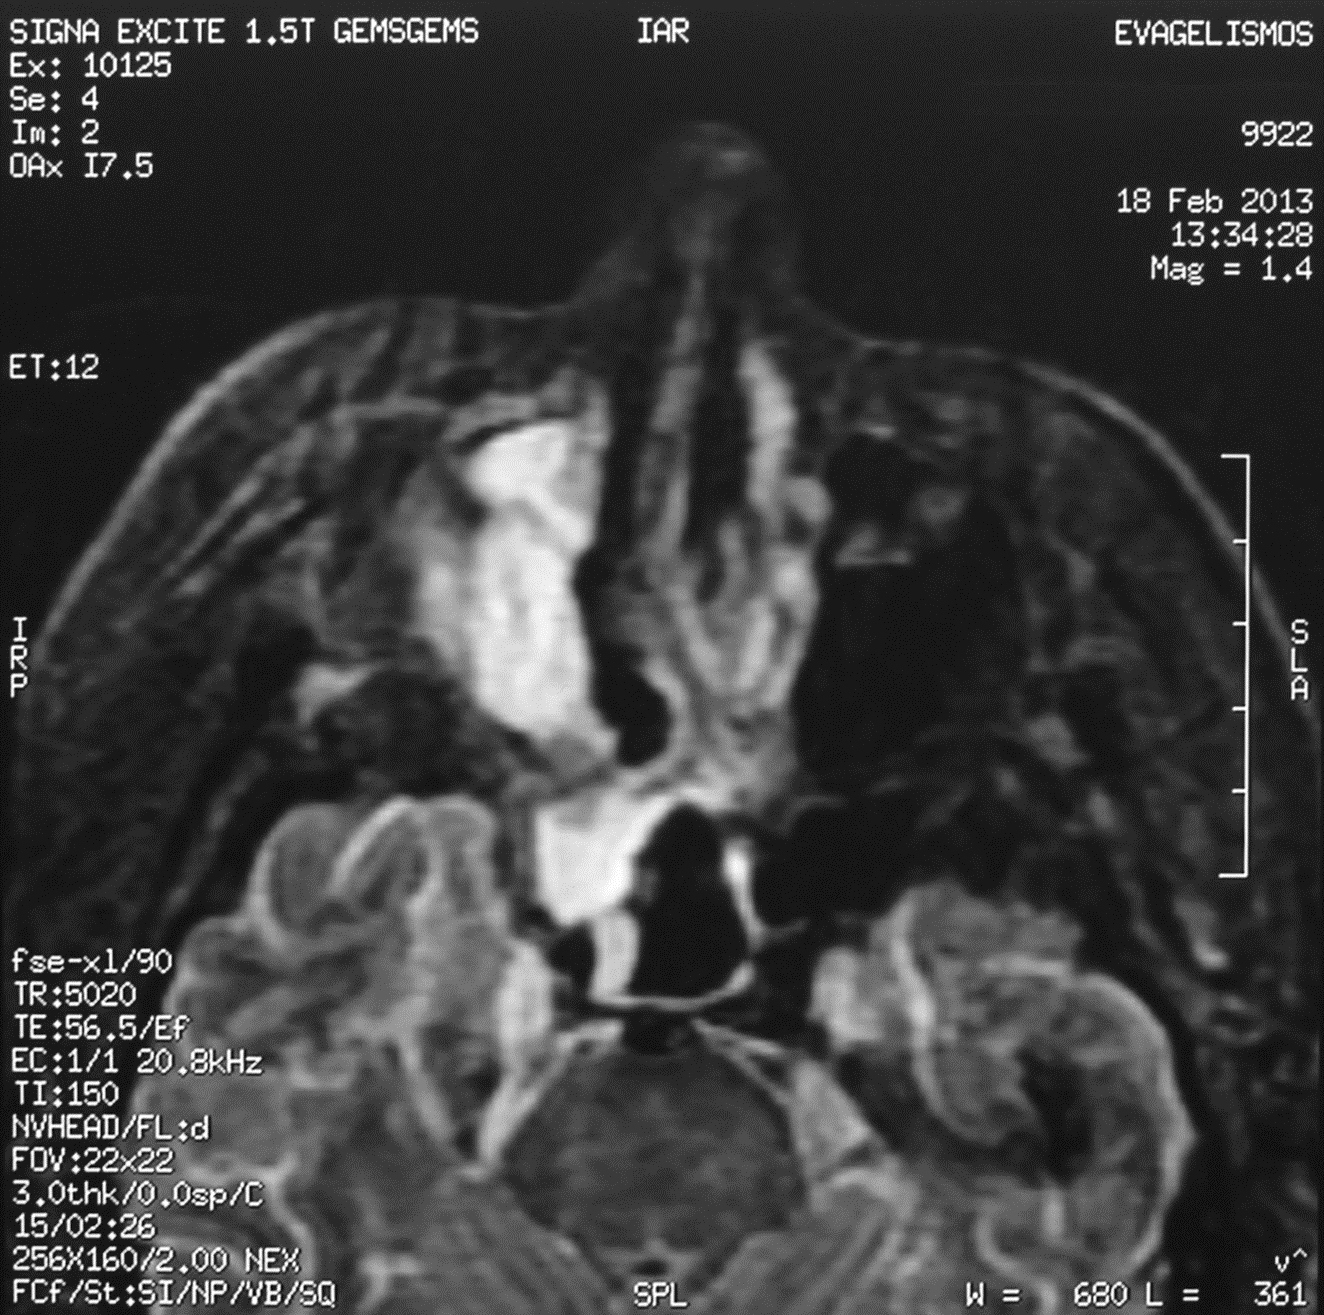

Invasive aspergillosisusually occurs in immunocompromised patients, particularly in patients with hematological malignancies because of severe and prolonged neutropenia and/orcytotoxic therapy. Therapy requires antifungal chemotherapy, with lipid-formulations of Amphotericin B or with azoles together with wide surgical excision of the fungal lesion. We report a case of invasive sino-orbital aspergillosis due to Aspergillus fumigatus in a patient with uncontrolled diabetes mellitus and small cell carcinoma. We support the notion that dual immunosuppression due to diabetes and small cell carcinoma with liver metastases was responsible for the invasive form of aspergillosis in this patient.Downloads